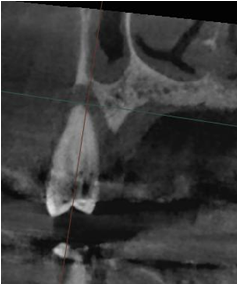

일반적으로 발치에서 임플란트 식립까지 2~3개월 이라는 긴 기간이 필요하지만

서울S에스치과는 많은 경험과 높은 기술력으로 하루 안에 발치와 임플란트 식립을 끝냅니다.

하지만, 모든 경우에 가능하지 않을 수 있어 정밀한 진단이 꼭 필요합니다.

(만약 잇몸질환이 심하다면 일정 기간의 잇몸뼈 치유기간을 가진 후 임플란트를 진행합니다.)